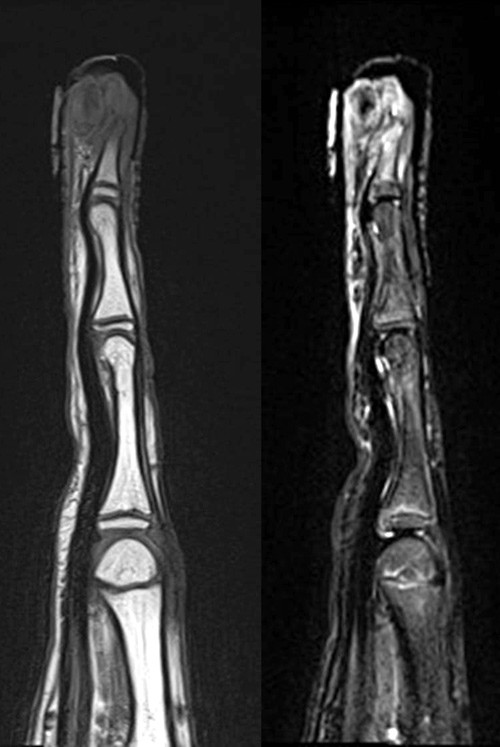

Det ble tatt nye mikrobiologiske prøver, ny biopsi i ledningsanestesi og røntgen- og MR-undersøkelse av finger og hånd. Gutten ble utskrevet fra hudavdelingen i påvente av resultatet fra den nye biopsien. Røntgen viste destruksjon ytterst i ytterfalangen (fig 2). MR viste en bløtdelsoppfylling ytterst på 3. finger som målte 15 × 15 × 18 mm. Det var infiltrasjon i hud og beinmargsødem i resten av ytterfalangen (fig 3). Den nye biopsien viste tallrike blodkar og epitel med mye granulocytter. Det var ingen tegn til mitoser eller neoplasi.

Håndkirurgen anbefalte å ta kontakt med ortoped i sarkomgruppen. MR-bilder ble oversendt sammen med biopsiene som var tatt ved universitetssykehus og lokalsykehus. Bildene ble vurdert av radiolog og ortoped i sarkomgruppen. Vurderingen var at situasjonen var mest forenlig med en inflammatorisk tilstand. Biopsier fra både lokalsykehuset og universitetssykehuset ble vurdert av sarkompatolog, uten at det ble påvist malignitet. Ny og dypere biopsi ble anbefalt.